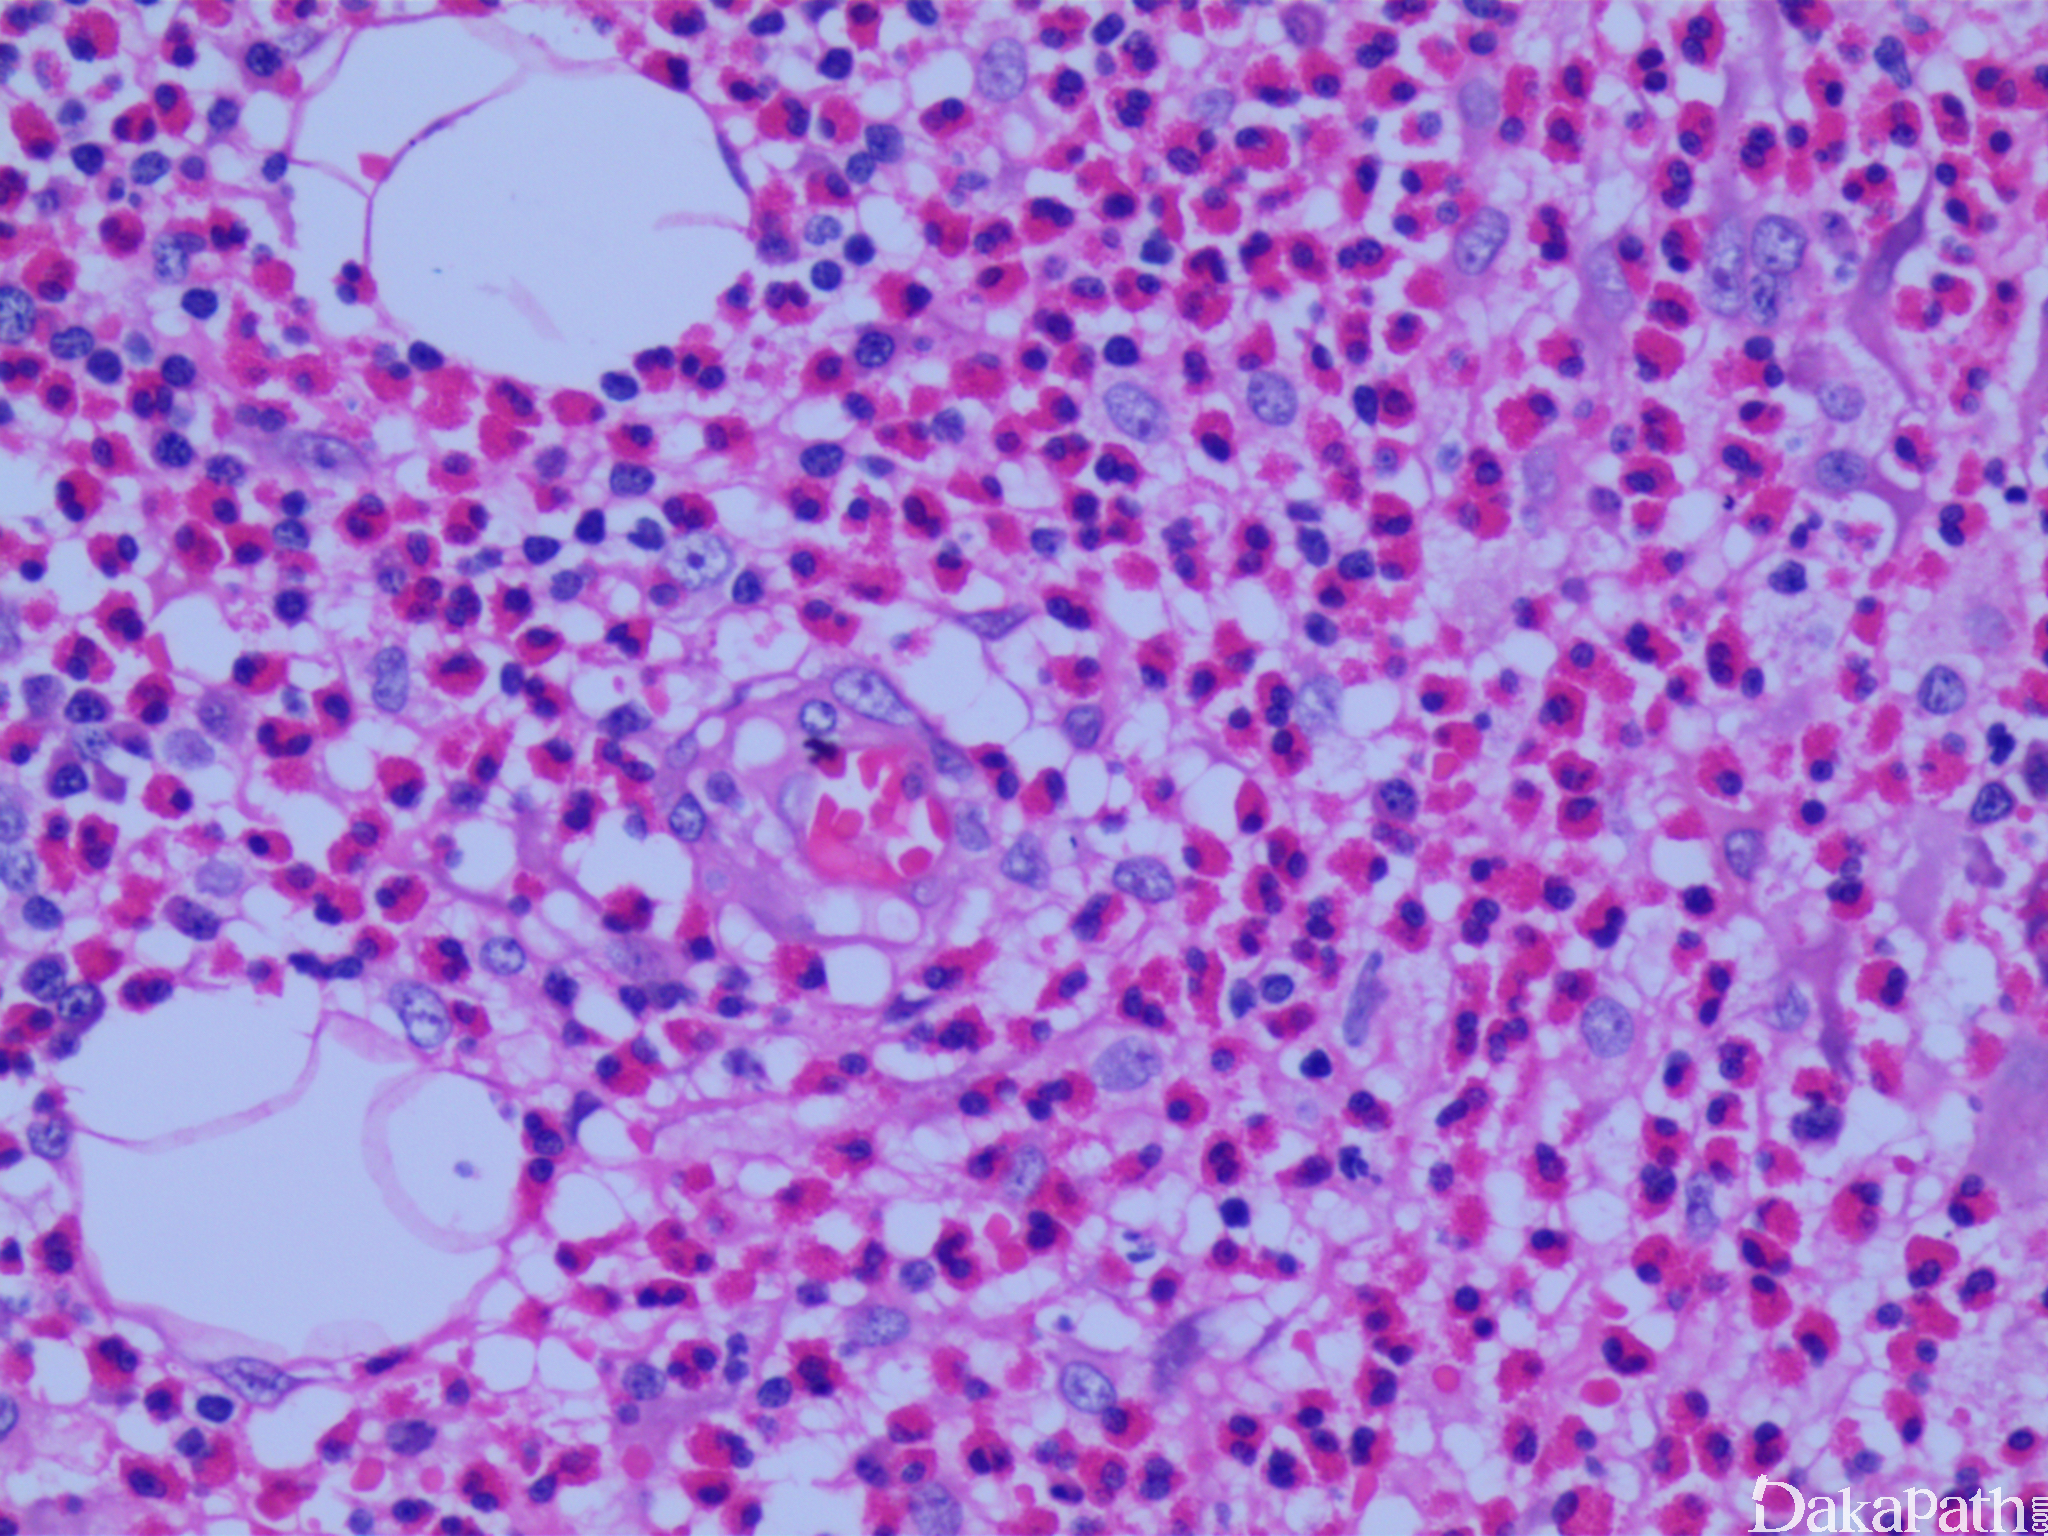

- 镜下以淋巴组织增生为主,旺炽型滤泡增生的背景中有纤细、嗜伊红色的蛋白质沉积物(IgE 以 FDC 网络的形式沉积)和生发中心内血管增生,少数病例内还可见到 Warthin-Finkeldey 型多核细胞及核碎片、间质纤维化;

- 滤泡间区显著的高内皮小静脉增生,伴淋巴细胞、浆细胞、嗜酸粒细胞和肥大细胞浸润;

- 常出现滤泡溶解,生发中心内和副皮质区可出现嗜酸粒细胞脓肿。